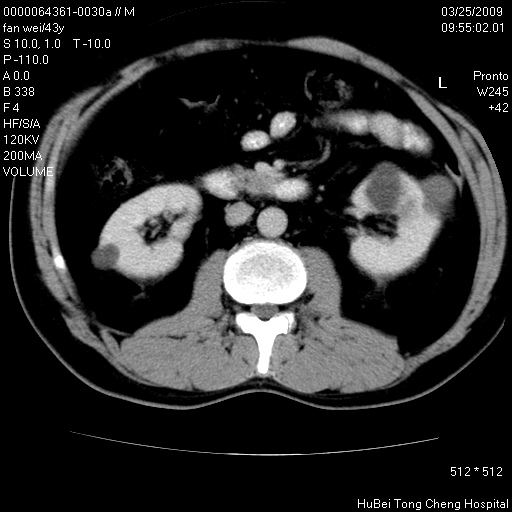

多囊肾的影像诊断标准:有阳性家族史,年龄<30岁,单侧或双侧肾脏有两个肾囊肿;30~59岁,两侧肾脏各有两个肾囊肿;60岁以上,每侧肾脏有4个囊肿。敏感性和特异性达86%和80%。

此病例影像诊断符合,要结合家族史,腰痛、血尿、尿路感染史,有无高血压等综合判断,如无相应的临床症状,本身病变也无意义了(个人观点)

双肾多发性囊肿

左肾体积变大,支持多囊肾。

双侧多囊肾!

双肾多发性囊肿   脂肪肝

囊肿数得清,肾功能正常,考虑多发肾囊肿.另外,右肾后极突向肾周间隙的那个病灶是不是错构瘤,请楼主调窗看看.